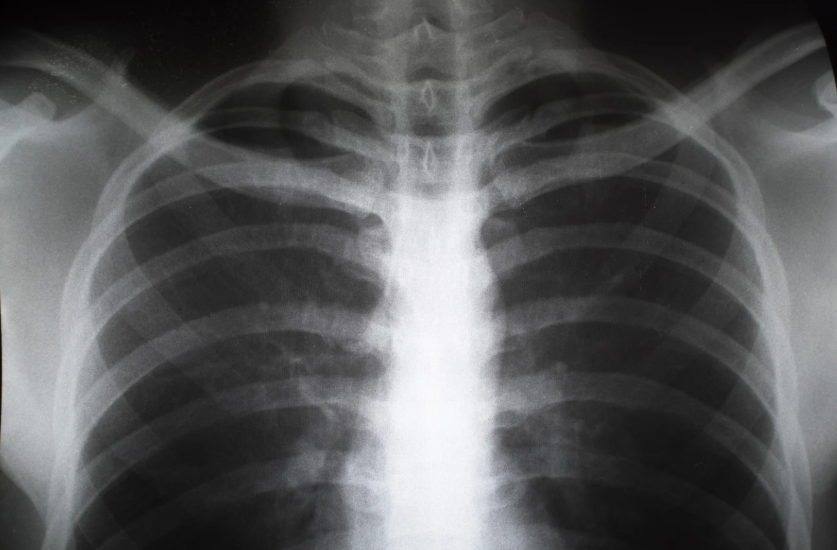

폐렴에 대하여

폐렴은 폐에 염증이 발생하는 질병으로, 주로 세균, 바이러스, 곰팡이, 또는 이물질에 의해 발생합니다. 이는 호흡기 질환 중에서 심각한 상태로 분류될 수 있으며, 적절한 치료가 이루어지지 않으면 생명에 위협을 줄 수 있습니다. 폐렴은 전 세계적으로 높은 사망률을 보이는 질병 중 하나로, 특히 면역력이 약한 고령자나 어린이에게 위험합니다.1. 폐렴의 원인폐렴은 주로 감염에 의해 발생합니다. 감염을 일으키는 원인은 크게 세균, 바이러스, 진균(곰팡이) 등으로 나눌 수 있습니다.세균성 폐렴: 가장 흔한 세균으로는 폐렴구균(Streptococcus pneumoniae), 황색포도상구균(Staphylococcus aureus), 인플루엔자균(Haemophilus influenzae) 등이 있습니다. 세균에 의한 ..